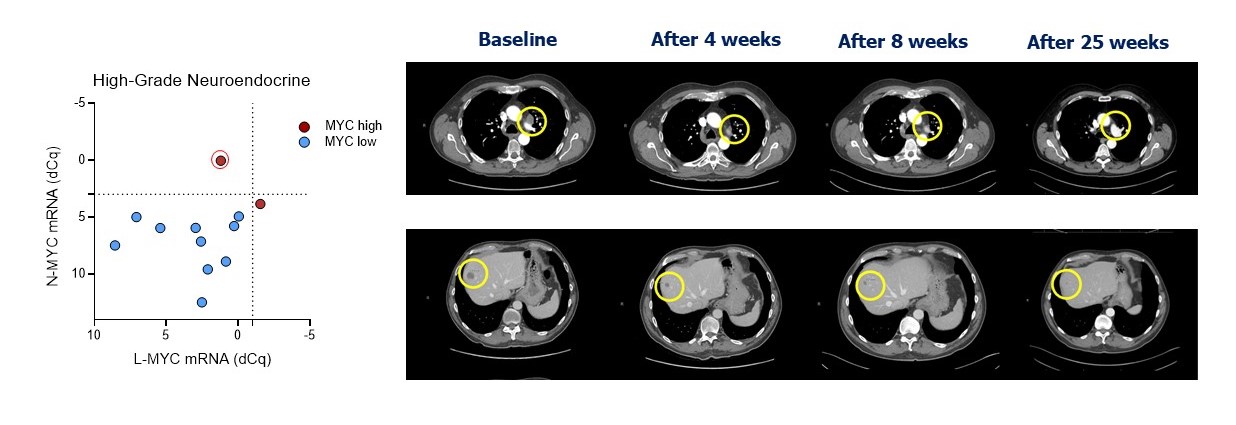

MRT-2359活性的进一步证据显示在图22中,它显示了在接受过重度治疗的高级别NE膀胱癌患者中证实的PR。患者既往有四线治疗,包括多线化疗和帕博利珠单抗。基线肿瘤活检显示高N-MYC表达。患者在前5天服用2毫克后出现4级中性粒细胞减少(不是剂量限制性毒性)导致剂量减少至1毫克,随后出现4级血小板减少(被认为是剂量限制性毒性),导致治疗中断并进一步剂量减少至0.5毫克。CT扫描显示确诊PR,目标病变持续缩小,从首次评估时的-31 %降至治疗11个月后的-89 %。